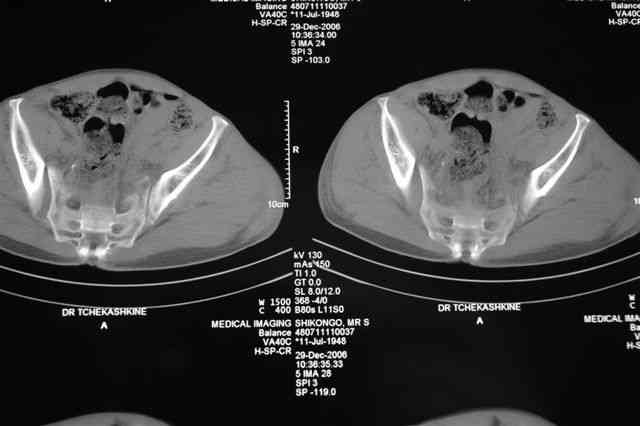

Уважаемые коллеги, Мужчина 58 лет в результате ДТП получил переломы 5-6-7 ребер справа (п\к эмфизема), вертикально-ротационно нестабильное повреждение тазового кольца, подвертельный перелом левого бедра, перелом внутр. лодыжки справа, пяточной кости справа.

Гемодинамика стабильна, НВ 10,2 г/л, Общ ан.крови, мочи - без патологии, Повреждения внутр. органов нет.

По техническим причинам стабилизация переломов в день травмы не была выполнена. До сегодняшнего дня находился на вытяжении.

Какова оптимальная последовательность фиксации на ваш взгляд: